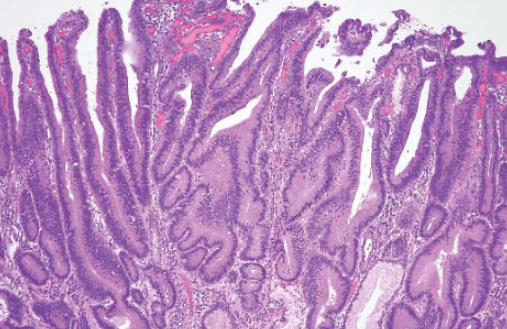

1. 위 선종이란 정확히 무엇인가?

위 선종은

위 점막 세포가 비정상적으로 증식해 생긴 ‘양성 종양’

입니다.

하지만 여기서 중요한 점은 단순한 혹(폴립)과 다르다는 것입니다. 위 선종은 세포 모양이 정상과 달라진 ‘이형성’ 단계입니다. 즉, 세포 구조가 변형된 상태로 암으로 발전할 가능성이 존재하는 병변입니다.

감염이 지속되면 점막 손상 → 위축성 위염 → 장상피화생 → 선종 → 암으로 이어질 가능성이 있습니다.

③ 위축성 위염·장상피화생

위 점막이 얇아지고 구조가 변형된 상태입니다.

이 단계는 위암 발생 위험이 높아지는 전 단계입니다.